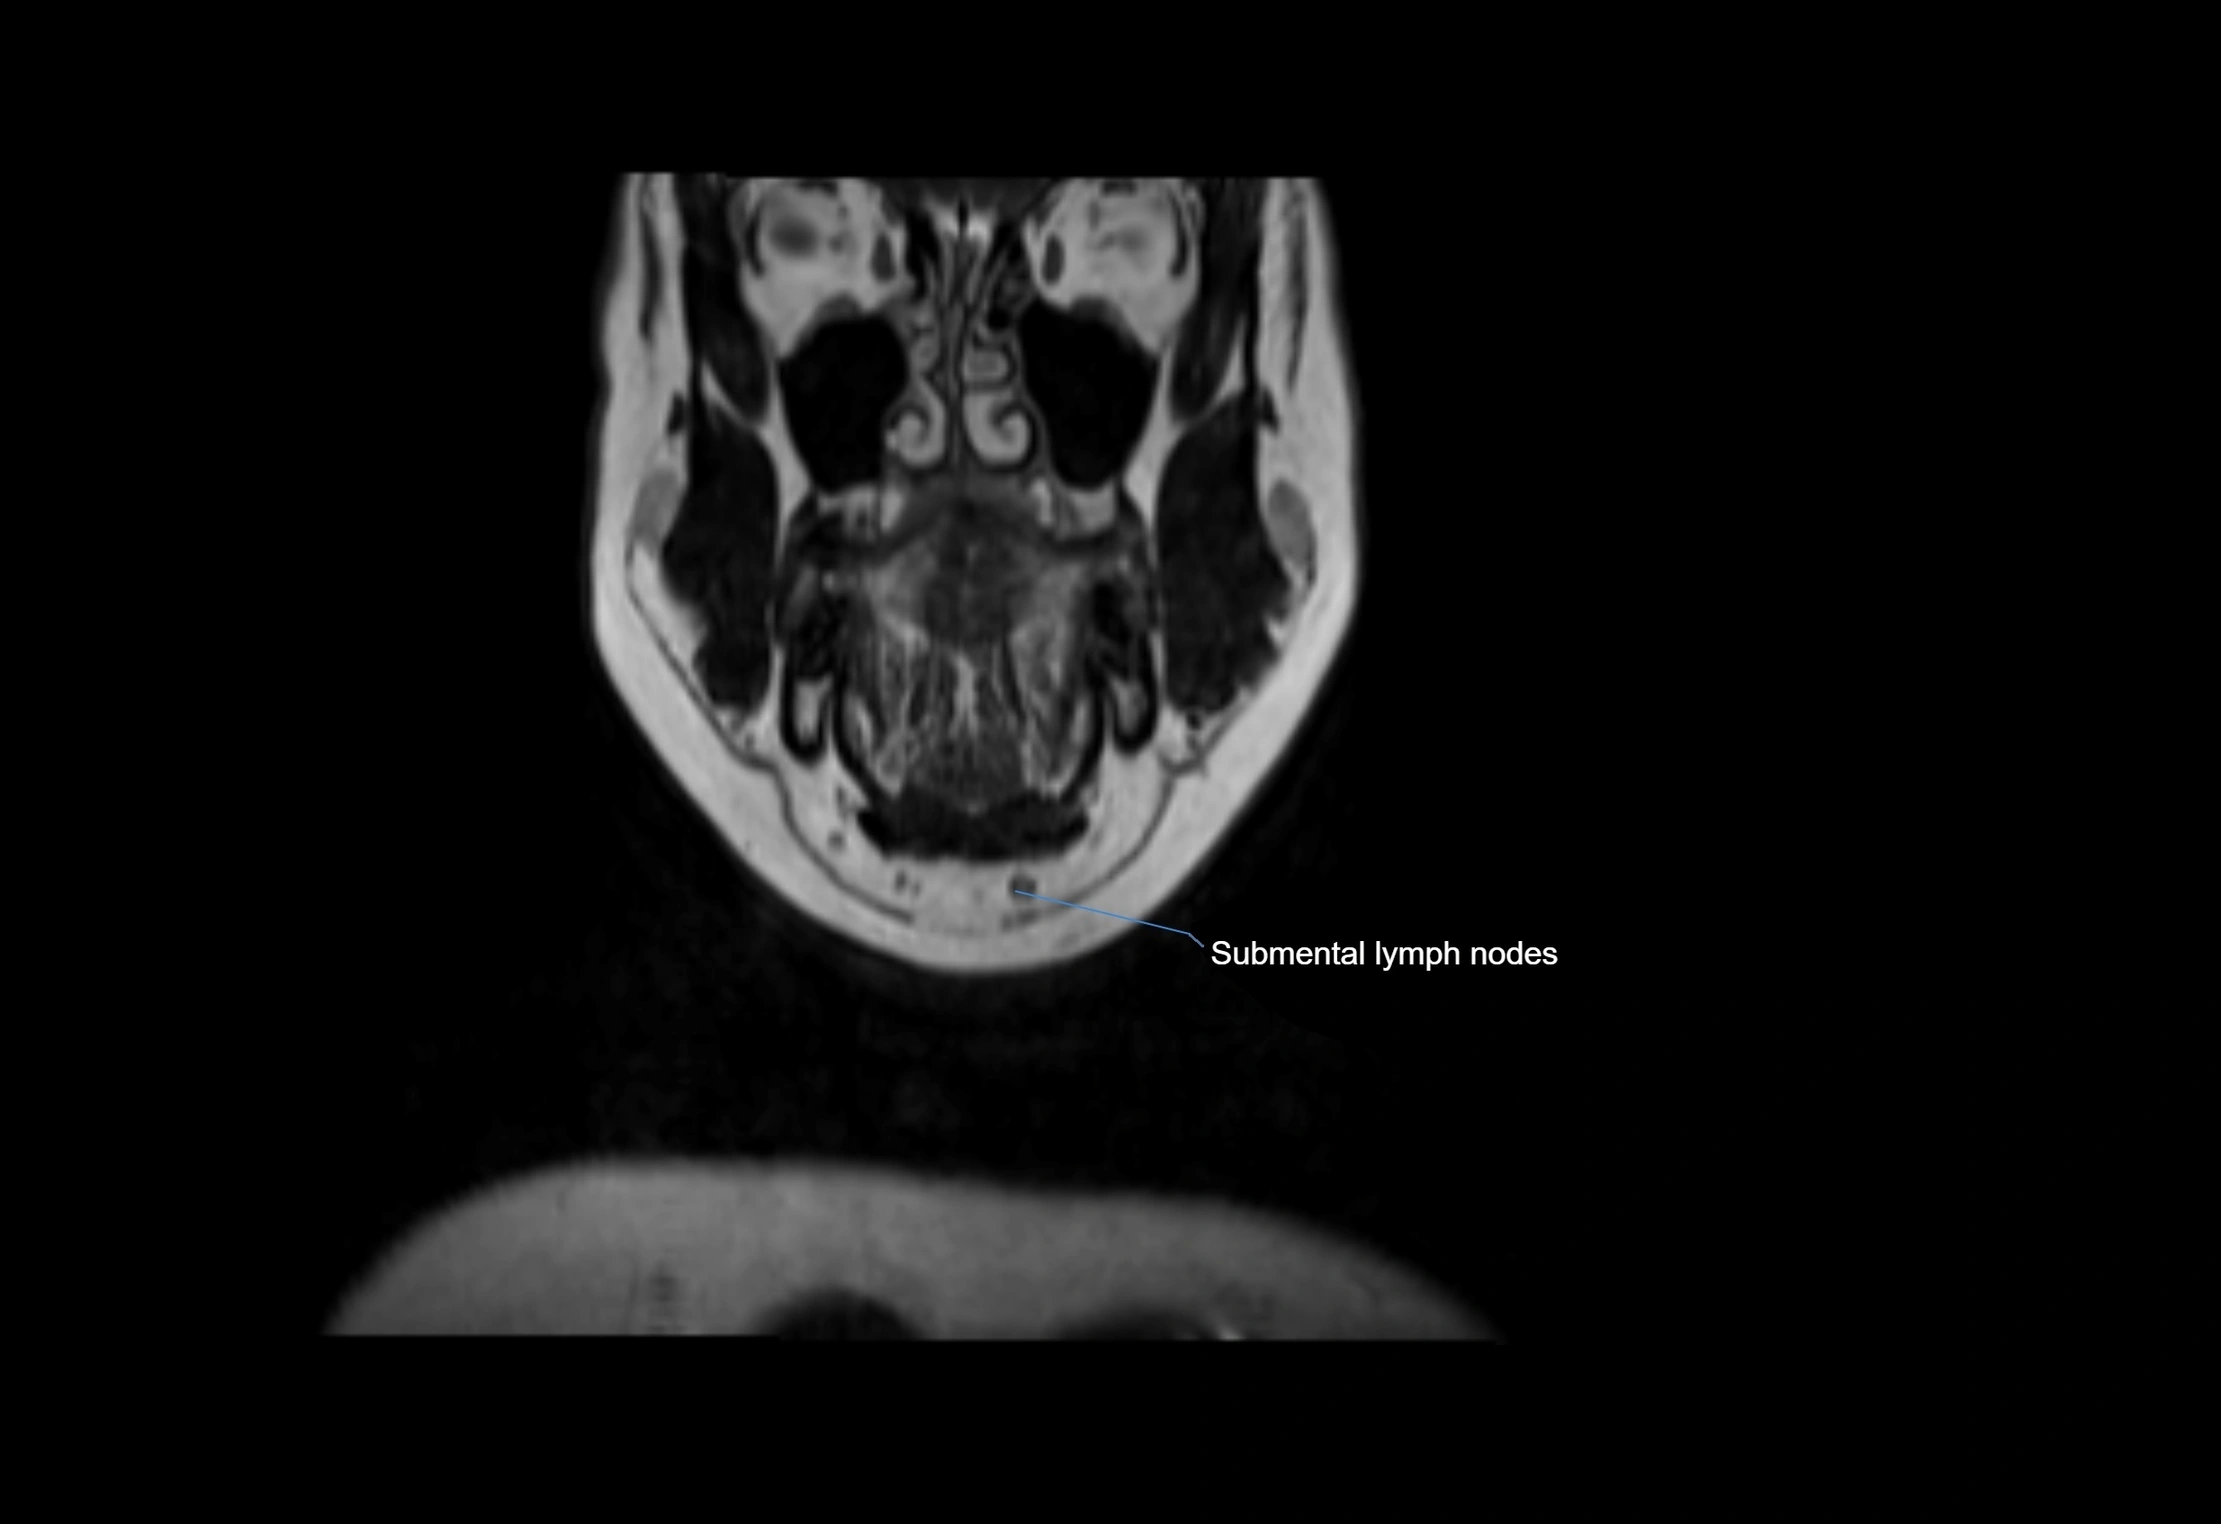

MRI Appearance

T1-weighted images:

• Normal accessory nodes appear as small, oval hypointense to intermediate signal structures within subcutaneous fat

• Surrounded by hyperintense fat, enhancing contrast for visualization

• Pathological nodes may appear enlarged or rounded, sometimes with cortical thickening

T2-weighted images:

• Nodes show intermediate signal, with surrounding fat bright

• Useful for detecting edema, inflammation, or infiltration

• Fatty hilum may appear slightly hyperintense relative to cortex

MRI images

image